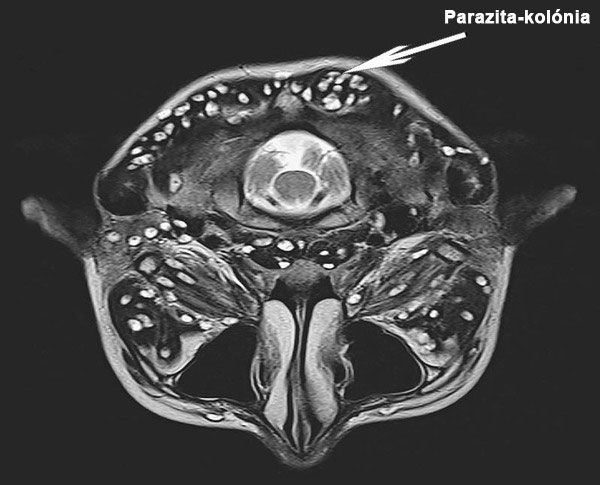

Ha papillómák vannak az emberi testen, lehetséges, hogy a halálos paraziták kolóniája már megtelepedett a belső szervekben és felfalja a szöveteket.

2. A méhet paraziták telepe fertőzte meg. Sajnos már nem lehetett megszabadulni tőlük, mivel a paraziták és lárváik teljesen kitöltötték a páciens méhét, és többször is szaporodtak. Ezért el kellett távolítani. A nőt sikerült megmenteni. Azonban a szervezetében olyan súlyos volt a mérgezés, hogy a méheltávolítás után speciális eljárásokon kellett átesnie, és sajnos három évvel később meghalt.